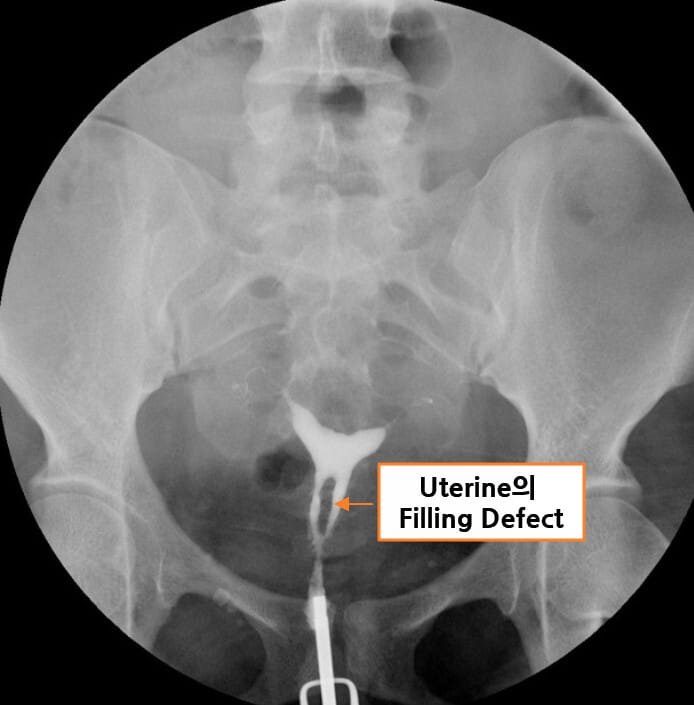

| 자궁난관조영술(HSG) |

| – 자궁강의 불규칙한 윤곽, 충만 결손(filling defect), 자궁강 일부 또는 전부의 소실이 관찰됩니다. |